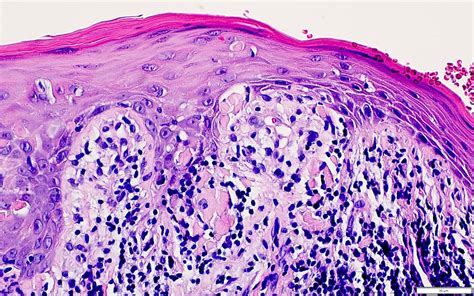

At its core, Erosive Lichen Planus is an autoimmune inflammatory condition. While the exact cause remains unknown, it occurs when the body's immune system mistakenly attacks the lining cells of the mucous membranes. This persistent inflammation leads to the breakdown of the tissue, resulting in painful, red, and eroded areas that are often rimmed with white, radiating lines known as Wickham striae. Because it is a chronic condition, patients often experience periods of remission followed by painful flares.

Identifying the condition early is vital, as the chronic inflammation and constant cell turnover associated with this form have been linked, in rare instances, to an increased risk of oral cancer. Therefore, consistent monitoring by a dental professional or an oral medicine specialist is non-negotiable for those diagnosed with the condition.

Because the disease state can change, you should view your dental team as your primary partners in health. Regular check-ups are not just for cleaning your teeth; they are essential for conducting an oral cancer screening. A biopsy might be required if the clinical appearance of a lesion changes or if it does not respond to standard treatment protocols. Never skip these appointments, as early detection of any tissue transformation offers the best possible prognosis.